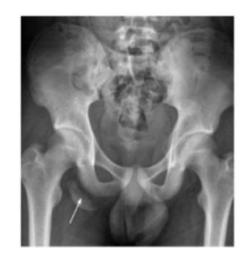

Bilateral Neck of Femur Fracture

Findings:

- Adult patient

- Osteoporotic bone changes

- Bilateral fracture neck of femur

Recommended additional imaging:

- CT scan for further evaluation